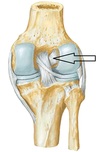

PCL

Attachment of ACL